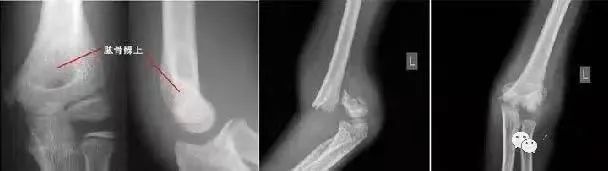

(6)肱骨髁上骨折

肱骨外髁骨折:肿胀及压痛局限于肘外侧,有时可触及骨折块;X片摄片桡骨纵轴线不通过肱骨小头骨化中心。

肱骨髁上骨折:肿痛较明显,呈环周压痛;X线片示骨折线不波及关节面,桡骨纵轴线通过肱骨小头骨化中心。

肱骨小头骨折:单纯的肱骨小头骨折多见于成人,合并部分外髁的肱骨小头骨折以儿童多见。亦有肘外侧及肘部的肿胀、疼痛,功能障碍;肘关节伸屈活动受限,尤其屈曲90-100°,常发生肘部疼痛加重并有阻力感觉;X线表现常有特征性,需仔细观察正、侧位X线片。